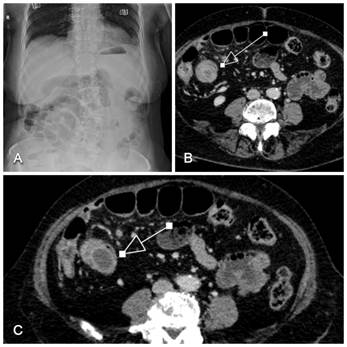

An abdominal ultrasound identified a non-compressible, "target-like" structure in the right half of the abdomen, which was highly suggestive of ileo-ileal invagination. Subsequent multi-slice computed tomography (MSCT) confirmed a long-segment ileo-ileal intussusception in the terminal ileum (Figure 1). Imaging also revealed distended bowel loops with air-fluid levels and several reactive subcentimeter mesenteric lymph nodes, raising suspicion of a potential neoplastic lead point.

Figure 1: Diagnostic Imaging of Adult Ileal Intussusception.

(A) Plain abdominal radiograph showing signs of non-specific small bowel obstruction, including distended loops in the mid-abdomen and a relative paucity of colonic gas. (B) Axial contrast-enhanced MSCT scan showing the pathognomonic "target sign" (indicated by the pointer) in the right half of the abdomen, representing the concentric layers of the

intussusceptum within the intussuscipiens. Dilated, fluid-filled bowel loops are seen proximal to the lesion. (C) A different axial MSCT level further distal, demonstrating the presence of mesenteric fat and enlarged lymph nodes within the intussuscipiens, serving as a suspicious lead point and confirming ileo-ileal invagination (pointer). Note the absence of high-grade air-fluid levels at this early stage.